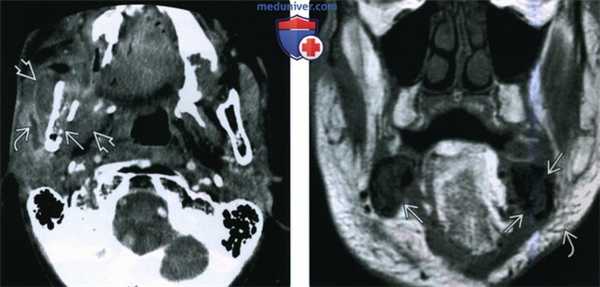

(Слева) При аксиальной КТ с КУ определяются признаки остеорадионекроза нижней челюсти справа, осложненного инфекцией жевательного пространства. Определяется дефект кортикальной пластинки, а также выраженный отек околоушной железы и жевательных мышц. Визуализируется расширенный проток околоушной железы, заполненный воспалительным дебрисом.

(Справа) При корональной МРТ Т1ВИ определяется диффузное замещение сигнала, типичного для жира, в костном мозге. Визуализируются также множеавенные дефекты кортикальной пластинки. Уплотнение и отек подкожной жировой ткани также часто обнаруживаются при ОРН нижней челюсти.

(Слева) При аксиальной КТ с КУ определяется остеорадионекроз нижней челюсти справа, осложненный инфицированием жевательного пространства. Определяется также нарушение целостности кортикальной пластинки и диффузный, выраженный отек жевательных мышц и околоушной слюнной железы, расширение ее выводного протока, заполненного дебрисом воспалительного характера.

(Справа) При МРТ Т1ВИ в корональной проекции определяется диффузное замещение сигнала, в норме наблюдающегося в костном мозге, и характерного для жира. Пристствуют множественные участки нарушения целостности кортикальной пластинки. Индурация и отек подкожных тканей являются часто встречающимися изменениями при остерадионекрозе нижней челюсти.